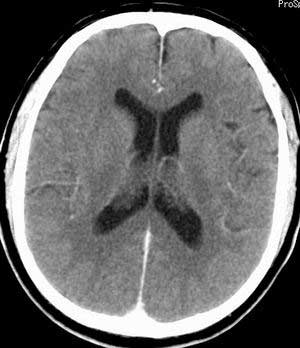

脑实质密度均匀,未见异常密度灶,脑沟裂池室形态大小正常,中线结构居中.

正常头颅ct表现

正常颅脑ct

正常颅脑ct片。

颅内未见异常,属正常头颅ct表现,建议薄层扫描内耳。